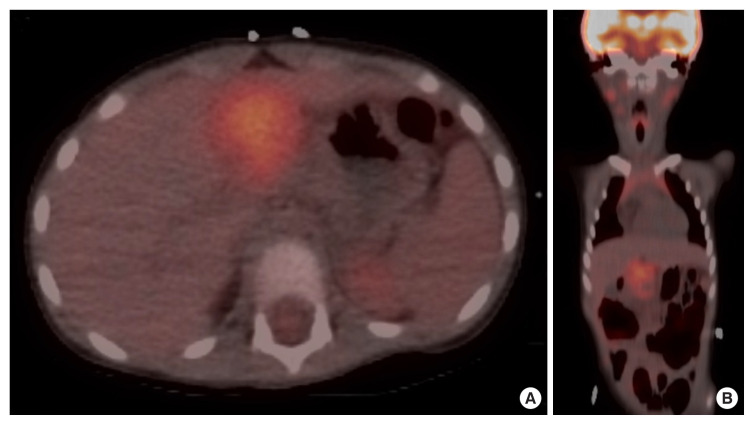

Extraosseous Ewing sarcoma is a rare and aggressive malignancy belonging to the Ewing sarcoma family of tumors, primarily affecting soft tissues such as the pelvis, retroperitoneum, and chest wall. Although it predominantly involves these soft tissues, extraosseous Ewing sarcoma can also occur in solid organs, including the pancreas. Here, we present a rare case of a 4-year-old girl diagnosed with primary extraosseous Ewing sarcoma of the pancreas.

Abstract Image